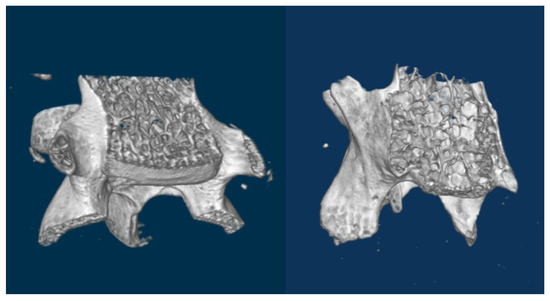

The cartilage covering the femoral head in hip joints mineralizes. It converts to a thick bony layer, losing the elastic properties of the chondral tissue (Figure 2). Osteoarthritis is installed. On the other hand, subchondral bone remains dense until the age of 80 weeks.

Figure 2.

(Left): 7 weeks (healthy) femoral head section. Outer cartilagenous layer is evident. (Right): 80 weeks (osteoarthritic) femoral head section. Cartilage has completely mineralized.